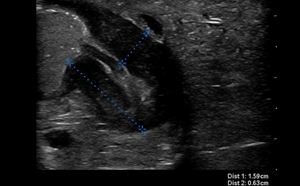

Pediatric Pyloric Stenosis